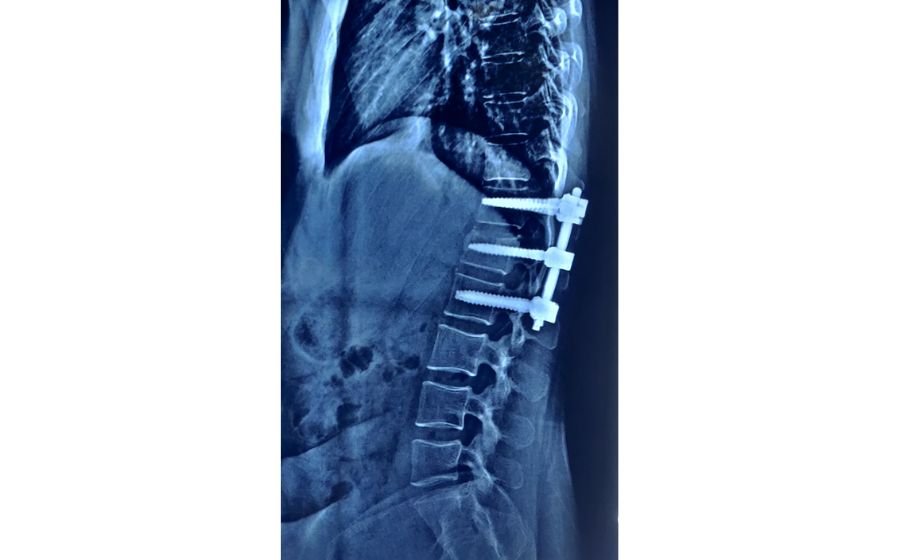

Fracture Fixation

Fracture fixation is performed to stabilize broken bones in the spine after trauma, falls, or accidents. When a fracture is unstable or risks damaging the spinal cord or nerves, screws and rods are used to realign and support the injured segment. Modern minimally invasive techniques allow stabilization through small incisions, reducing pain and speeding up recovery. The goal is to restore spinal stability, protect nerve function, and help patients return safely to their daily activities.